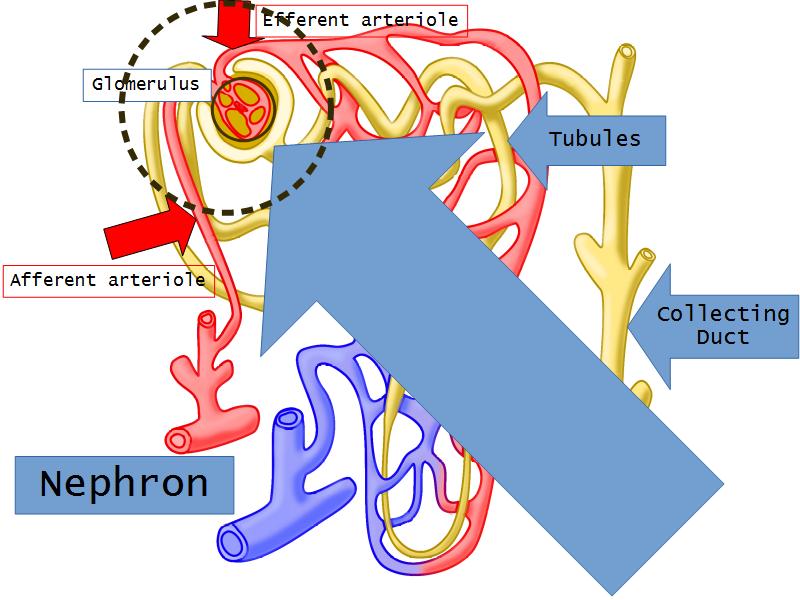

- Basic arrangement of nephrons and collecting tubules in the kidney

- Structure of the nephron and collecting tubules

- Make an annotated diagram of a nephron, including the juxtaglomerular apparatus. Indicate the flow of blood and water in each part, and how solutes are filtered, secreted and reabsorbed.

Nephron